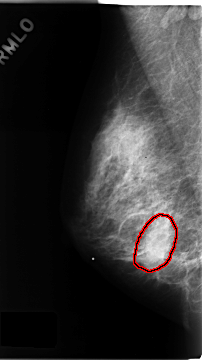

C_0162_1.RIGHT_MLO

RIGHT_MLO LINES 4680 PIXELS_PER_LINE 2624 BITS_PER_PIXEL 12 RESOLUTION 50 OVERLAY

FILE: C_0162_1.RIGHT_MLO.OVERLAY

TOTAL_ABNORMALITIES 1

ABNORMALITY 1

LESION_TYPE CALCIFICATION TYPE FINE_LINEAR_BRANCHING DISTRIBUTION CLUSTERED

LESION_TYPE MASS SHAPE IRREGULAR MARGINS ILL_DEFINED

ASSESSMENT 5

SUBTLETY 4

PATHOLOGY MALIGNANT

TOTAL_OUTLINES 1

BOUNDARY